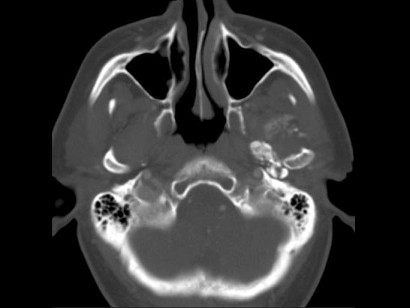

男,60岁,张口受限半年,CT检查如图所示,正确的描述或诊断是()

A.左侧颞颌关节周围软组织内见较多致密钙化影

B.左侧颞颌关节软组织未见肿胀

C.左侧颞颌关节面(颞骨面)骨质增生明显

D.左侧颞颌关节滑膜骨软骨瘤病

E.颞颌关节功能紊乱